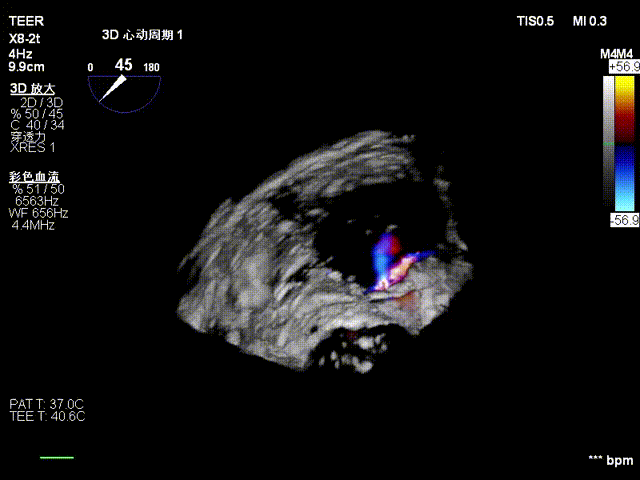

视频1:术前Bicom

视频2:二尖瓣2区后叶栓系

视频3:二尖瓣三维视图

患者全麻下行TEER手术。向睿副主任团队穿刺患者右侧股静脉,在X线及食道超声指导下完成房间隔穿刺(视频4)成功获得3.95cm穿刺高度(图4)。再将加硬导丝送至左上肺静脉,20F股静脉扩张鞘充分扩张股静脉穿刺部位,沿加硬导丝将可操纵导引导管(SGC)送入左房。延SGC送入XTR夹子完成骑跨,使用M旋钮使夹子指向二尖瓣(图5)(视频5)。调整Mitraclip输送系统顺利到达二尖瓣目标位置,TEE指导下左房内完成弹道测试和Orientation调整(视频6)。缓慢将XTR夹子送入左室,并三维再次确认夹子轴向和反流位置,缓慢上提夹子使夹臂成功捕获瓣叶(视频7),Gripper Down夹持前后瓣叶并缓慢关闭夹臂(视频9),夹持后反流降至微量(视频10),二尖瓣平均跨瓣压差2mmHg(图6)。评估后将夹子释放。释放后反流微量夹子稳定。术后复查超声证实夹合组织充分,显示微量残余分流。术后二尖瓣平均跨瓣压差2mmHg,肺静脉多普勒波形恢复正常。手术时间持续约1.5小时。